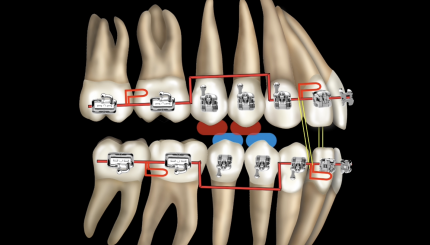

Класс 2 , низкий угол. Подход к лечению

Класс II, высокий угол. Подход к лечению.

Класс III, низкий и высокий угол. Подход к лечению

Клинический случай. Ребенок, II класс

Разбор кейса. MLD, ребенок, техника направленного роста